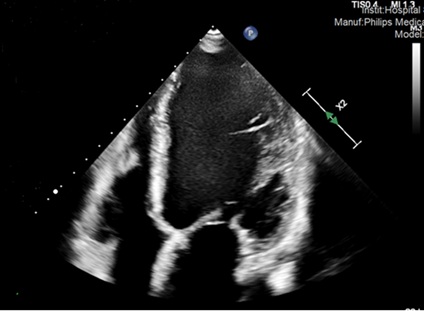

Ante sospecha de miocardiopatía dilatada, se realiza ecocardiograma que pone de manifiesto dilatación severa del ventrículo izquierdo con hipocinesia global severa y FEVI 32%, acompañado de ligera dilatación auricular izquierda e insuficiencia mitral funcional moderada con ligero derrame pericárdico.